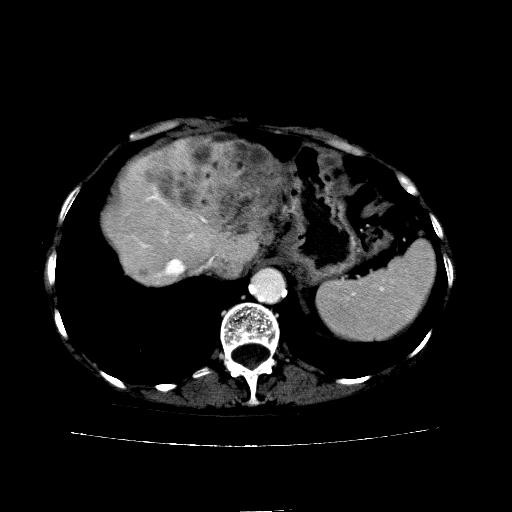

患者08年胆囊结石切除,之前没有做过ct,现在患者厌食。

平扫

看片子胆管里结石,肝上显示的占位会不会是胆管癌?大家帮忙看看,图像不太好,手头的处理文件没有,大致转换了一下,有原始图像数据